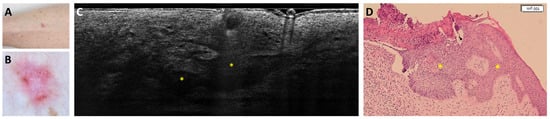

Dermal Mitoses Correlate with Surgical Burden in Lentigo Maligna Melanoma: PRAME for Margin Assessment